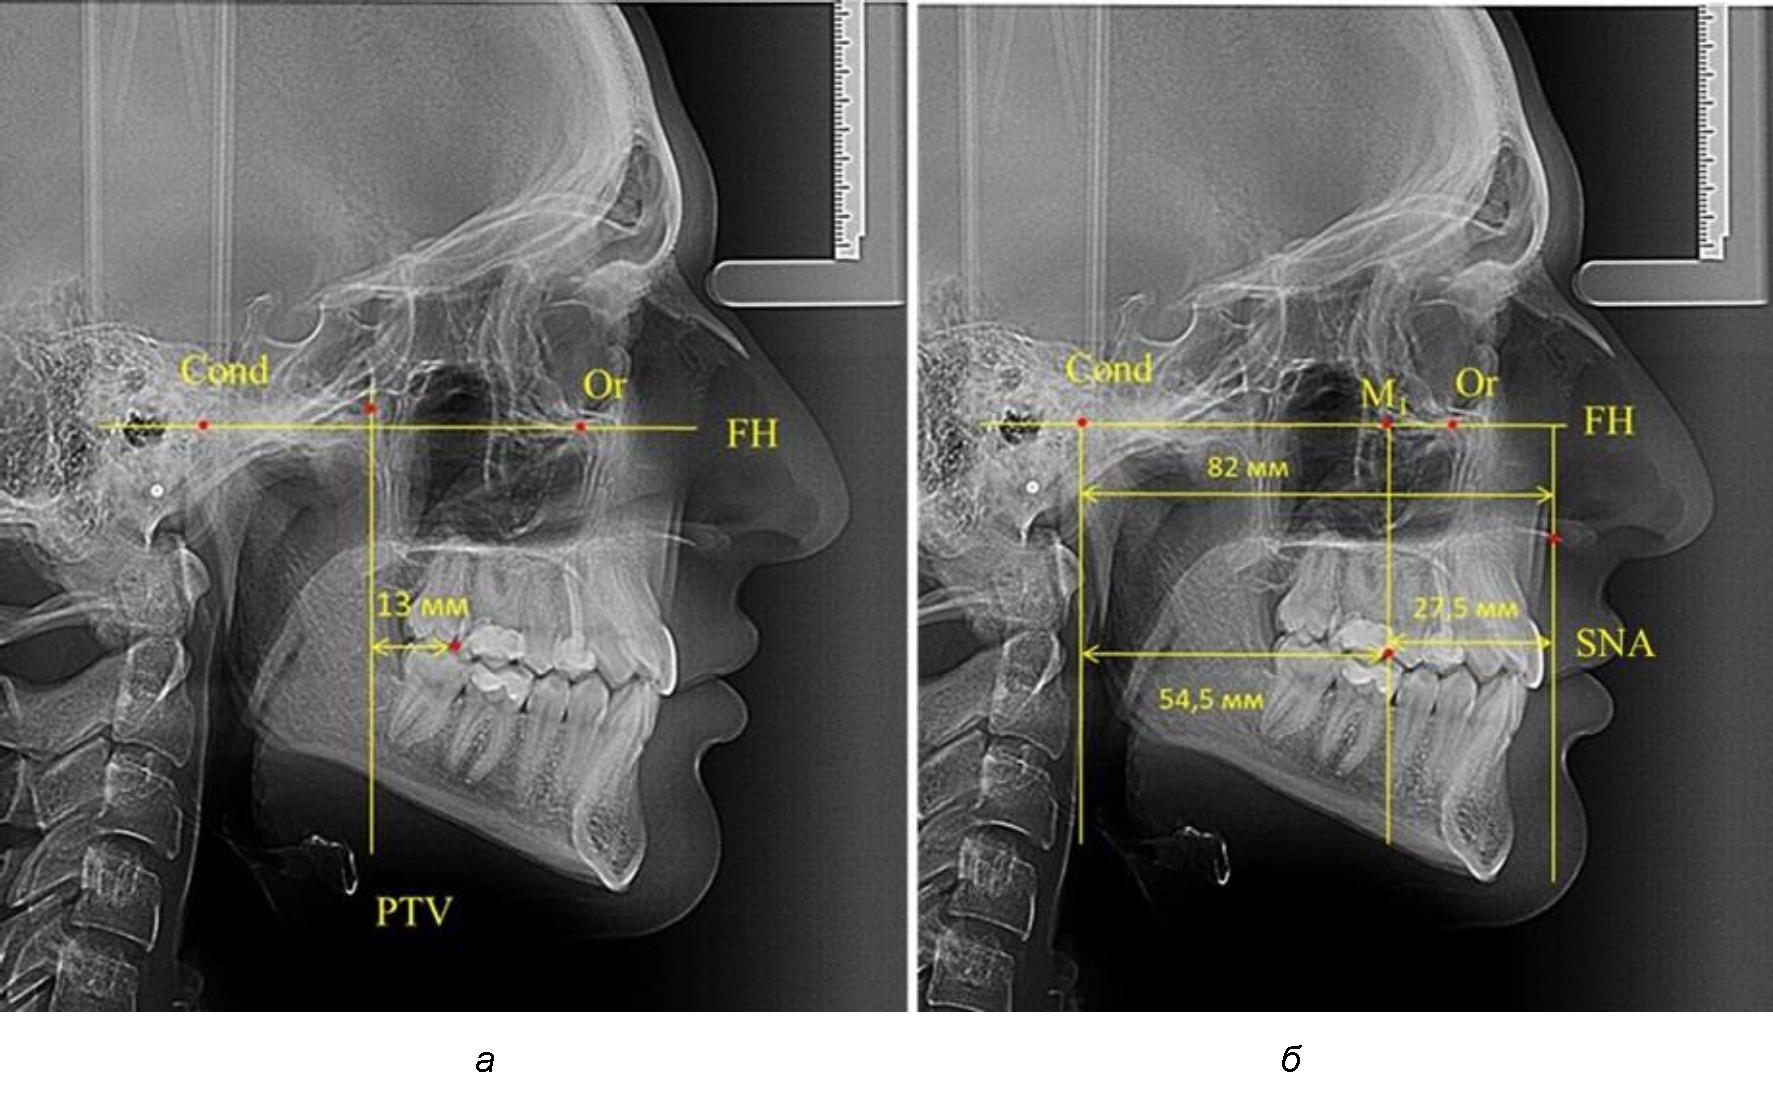

Рис. 1. Метод определения положения первых верхних моляров по Ralph E. McDonald (а) и по предложенному методу (б)

Так, при расстоянии от крыловидной вертикальной плоскости PTV до дистальной поверхности верхнего первого постоянного моляра в 13 мм сагиттальный размер гнатического отдела был 82 мм. При этом отношение кондилярно-спинального расстояния к кондилярно-молярному размеру (54,5) было близким к коэффициенту 1,5, что представлено на рис. 2.

При проведении анализа к Франкфуртской горизонтали проводили передний и задний перпендикуляры. Передний спинальный перпендикуляр проходил через выступающую точку передней носовой ости (spina nasalis anterior – SNA), а задний суставной перпендикуляр опускали из кондилярной точки Cond. Молярный перпендикуляр проводили через медиальную поверхность первого постоянного моляра. Указанная вертикаль отделяла замещающие зубы постоянного прикуса от добавочных зубов (постоянных моляров), что вполне логично для анализа положения первых постоянных моляров в гнатическом комплексе (рис. 1).